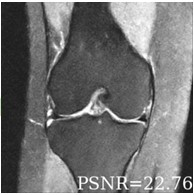

Deep learning based techniques achieve state-of-the-art results in a wide range of image reconstruction tasks like compressed sensing. These methods almost always have hyperparameters, such as the weight coefficients that balance the different terms in the optimized loss function. The typical approach is to train the model for a hyperparameter setting determined with some empirical or theoretical justification. Thus, at inference time, the model can only compute reconstructions corresponding to the pre-determined hyperparameter values. In this work, we present a hypernetwork based approach, called HyperRecon, to train reconstruction models that are agnostic to hyperparameter settings. At inference time, HyperRecon can efficiently produce diverse reconstructions, which would each correspond to different hyperparameter values. In this framework, the user is empowered to select the most useful output(s) based on their own judgement. We demonstrate our method in compressed sensing, super-resolution and denoising tasks, using two large-scale and publicly-available MRI datasets. Our code is available at https://github.com/alanqrwang/hyperrecon.